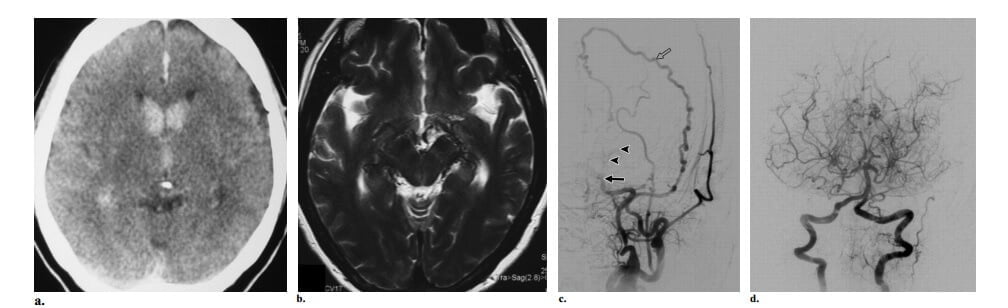

Bệnh moyamoya (tiếng nhật nghĩa là “khói thuốc lá”) là một bệnh lý tắc nghẽn ít gắp có nguồn gốc không rõ, về mặt kinh điển liên quan với các động mạch cảnh trong trên mấu giường yên, hố sau tương đối bình thường ở giai đoạn sớm. Thuật ngữ hội chứng moyamoya được dùng trong các trường hợp không thể xác định được nguyên nhân gốc (xơ vữa độngmạch, hội chứng Down, bệnh đa u sợi thần kinh, bệnh hồng cầu hình liềm hoặc một số bệnh khác). Thường có sự phát sinh rất nhiều mạch máu bàng hệ ở các nhánh xuyên vùng nền (các mạch máu moyamoya), đã được mô tả là hình ảnh khói thuốc lá trên hìnhchụp mạch máu não và các mạch máu bàng hệ xuyên màng cứng. Biểu hiện lâm sàng khác nhau giữa hai nhóm trẻ em và người lớn: hầu hết trẻ em có cơn thiếu máu thoáng qua hoặc nhồi máu não trong khi có một nửa số người lớn có xuất huyết nội sọ do vỡ các mạch máu bàng hệ moyamoya.

Manh mối hình ảnh học trên CT và MRI gồm sự hiện diện của nhiều tín hiệu flow voids thường thấy xuất phát từ bể nền và lan vào hạch nền hoặc đồi thị. Không có nidus thực sự nằm trong nhu mô não và không có dãn mạch máu (hình 11). Mặc dầu chẩn đoán có thể gợi ý bằng sự hiện diện của hẹp động mạch cảnh trong trên mấu giường yên hai bên trên hình chụp mạch CT và MR, nhưng chụp mạch máu vẫn còn cần thiết để đánh giá trước phẫu thuật cho việc tái tạo mạch máu của bệnh moyamoya. Tập hợp các đường bàng hệ thứ phát (các mạch máu bàng hệ moyamoya nhánh xuyên hạch nền, cấp máu xuyên màng cứng từ động mạch màng não giữa đến lối não và thông qua động mạch mắt đến các nhánh động mạch não trước) thường có thể được đánh giá chỉ bằng chụp DSA do kích thước nhỏ. Các nghiên cứu mới đây đã chứng minh rằng hình ảnh MR tưới máu và các khảo sát bảo tồn mạch máu não có thể chọn lựa trước phẫu thuật và theo dõi sau phẫu thuật sau khi phẫu thuật tái tạo mạch máu.

Hình 11: Bệnh moyamoya ở nữ 28 tuổi trải qua hai đợt xuất huyết nội sọ tái phát. (a) Axial CT cho thấy xuất huyết trong não thất. (b) Axial T2W thấy rất nhiều flow voids trong bể quanh gian não và quanh não giữa. Không thấy nidus. (c) Hình chụp động mạch cảnh trong thế trước sau thấy tắc động mạch cảnh trong trên mấu giường yên (mũi tên đặc) với rất nhiều mạch máu bàng hệ nhánh xuyên (đầu mũi tên). Cùng ghi nhận có cấp máu bàng hệ xuyên màng cứng từ động mạch màng não giữa (mũi tên hở). (d). Chụp động mạch cột sống trước sau cho thấy có liên quan các động mạch não sau, cùng với việc không có mạch máu bàng hệ hình khói thuốc lá gợi ý bệnh ở giai đoạn sau.